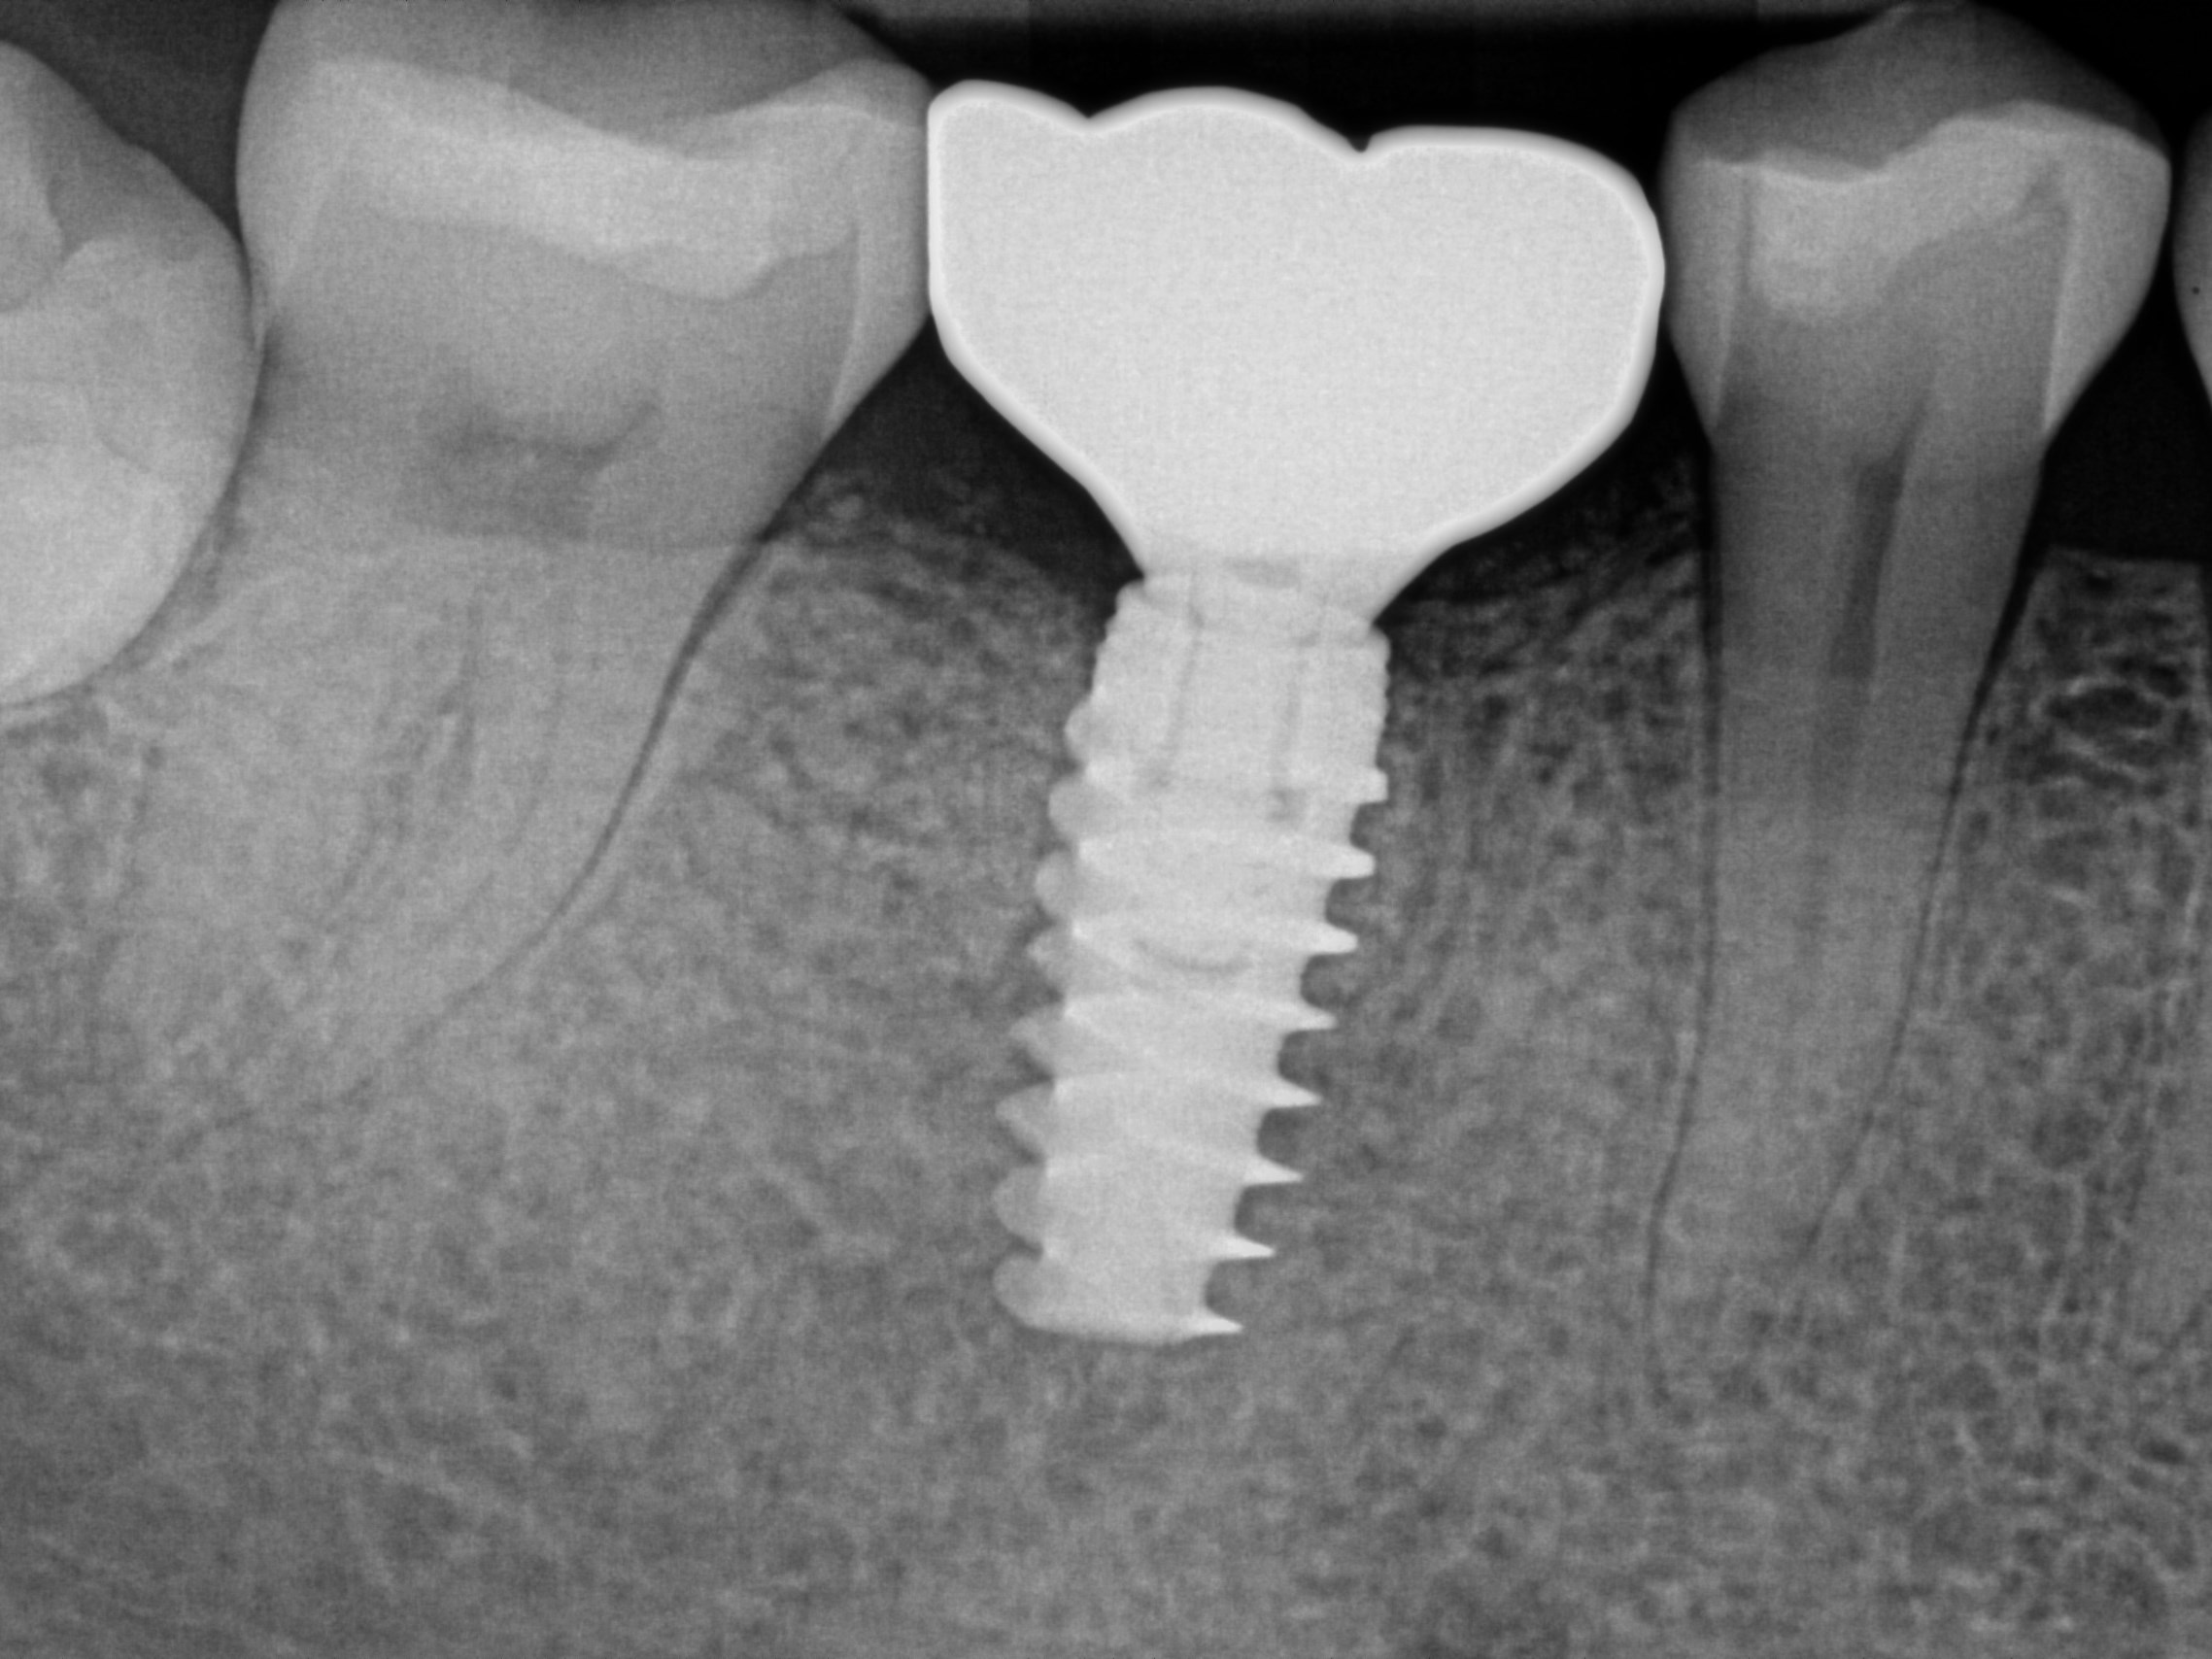

Custom Implant Crown

Procedure Details